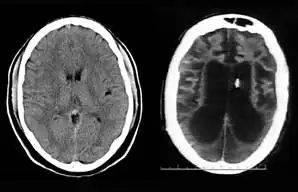

On August 10, 2001, on remand from the Florida Second District Court of Appeal, Judge Greer heard a motion from the Schindlers claiming that new medical treatment could restore sufficient cognitive ability such that Terri Schiavo herself would be able to decide to continue life-prolonging measures. The court also heard motions from the Schindlers to remove the guardian (Michael Schiavo) and to require Judge Greer to recuse himself. Judge Greer denied the motions and the Schindlers appealed to the Second District Court of Appeals. On October 17, 2001, the Court of Appeal affirmed the denials of the motions to remove and recuse. The Court of Appeals acknowledged that their opinion misled the trial court, and they remanded the question of Terri Schiavo's wishes back to the trial court and required an evidentiary hearing to be held. The court specified that five board certified neurologists were to testify. The Schindlers were allowed to choose two doctors to present findings at an evidentiary hearing while Schiavo could introduce two rebuttal experts. Finally, the trial court itself would appoint a new independent physician to examine and evaluate Terri Schiavo's condition. These decisions, all published in a single order by the Florida Second District Court of Appeal,[37] came to be known by the court as Schiavo III in its later rulings. In October 2002, on remand by the Second District Court of Appeal, an evidentiary hearing was held in Judge Greer's court to determine whether new therapy treatments could help Terri Schiavo restore any cognitive function. In preparation for the trial, a new computed axial tomography scan (CAT scan) was performed, which showed severe cerebral atrophy. An EEG showed no measurable brain activity. The five physicians chosen were William Maxfield, a radiologist, and four neurologists: William Hammesfahr, Ronald Cranford, Melvin Greer and Peter Bambakidis.[38]

The five doctors examined Terri Schiavo's medical records, brain scans, the videos, and Terri herself. Cranford, Greer, and Bambakidis testified that Terri Schiavo was in a persistent vegetative state (PVS). Maxfield and Hammesfahr testified that she was in a minimally conscious state. As part of the court-ordered medical exam, six hours of video of Terri Schiavo were taped and filed at the Pinellas County courthouse. The tape included Terri Schiavo with her mother and neurologist William Hammesfahr. The entire tape was viewed by Judge Greer, who wrote, Terri "clearly does not consistently respond to her mother". From that six hours of video, the Schindlers and their supporters produced six video clips intended to support their case, totaling less than six minutes, and released those clips to public websites.[1] Judge Greer ruled that Terri Schiavo was in a PVS, and was beyond hope of significant improvement. The trial court order was particularly critical of Hammesfahr's testimony, which claimed positive results in similar cases by use of vasodilation therapy, the success of which is unsupported in the medical literature.[39] This ruling was later affirmed by Florida's Second District Court of Appeal, which stated that "this court has closely examined all of the evidence in the record", and "we have ... carefully observed the video tapes in their entirety." The court concluded that "if we were called upon to review the guardianship court's decision de novo, we would still affirm it." This decision by the Second District Court of Appeals[40] came to be known as Schiavo IV in later rulings.

Schiavo's body was taken to the Office of the District 6 Medical Examiner for Pinellas and Pasco counties, based in Largo, Florida. The autopsy was conducted on April 1, 2005, and revealed extensive brain damage. The manner of death was certified as "undetermined." The autopsy was led by Chief Medical Examiner Jon R. Thogmartin. In addition to consultation with a neuropathologist (Stephen J. Nelson), Thogmartin also arranged for specialized cardiac and genetic examinations to be made. The official autopsy report[32] was released on June 15, 2005. In addition to studying Terri Schiavo's remains, Thogmartin scoured court, medical and other records and interviewed her family members, doctors and other relevant parties. Examination of Schiavo's nervous system, by neuropathologist Stephen J. Nelson, revealed extensive injury. The brain itself weighed only 615 g (21.7 oz), only half the weight expected for a female of her age, height, and weight, due to the loss of a massive number of neurons. Microscopic examination revealed extensive damage to nearly all brain regions, including the cerebral cortex, the thalamus, the basal ganglia, the hippocampus, the cerebellum, and the midbrain. The neuropathologic changes in her brain were precisely of the type seen in patients who enter a PVS following cardiac arrest. Throughout the cerebral cortex, the large pyramidal neurons that comprise some 70% of cortical cells – critical to the functioning of the cortex – were completely lost. The pattern of damage to the cortex, with injury tending to worsen from the front of the cortex to the back, was also typical. There was marked damage to important relay circuits deep in the brain (the thalamus) – another common pathologic finding in cases of PVS. The damage was, in the words of Thogmartin, "irreversible, and no amount of therapy or treatment would have regenerated the massive loss of neurons."[70]